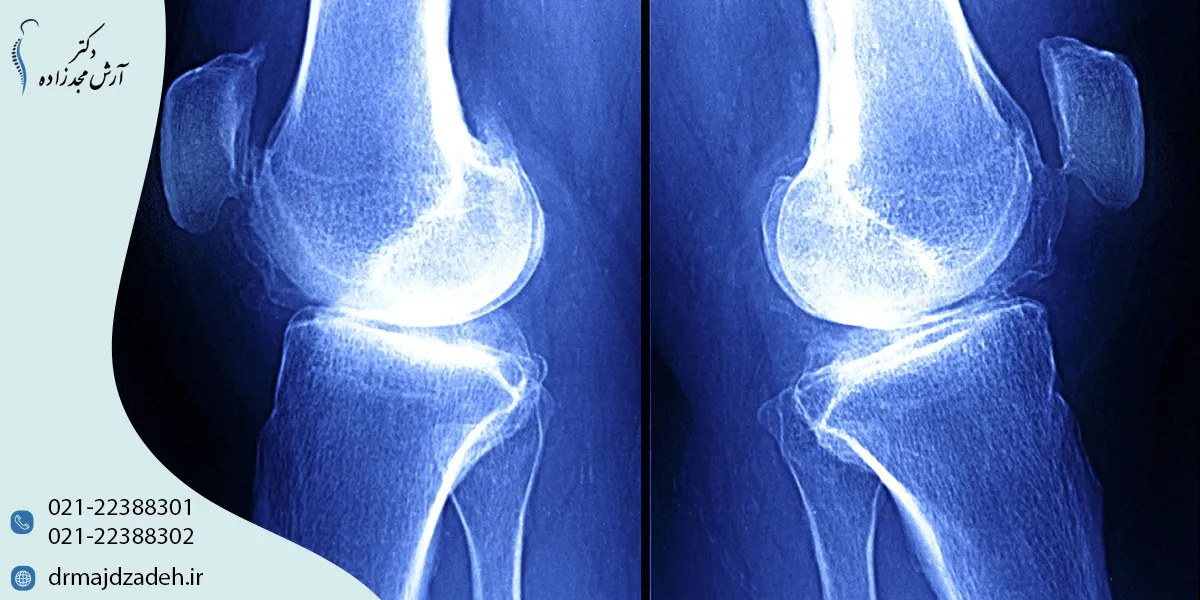

تشخیص آرتروز زانو

تشخیص بهموقع آرتروز مفاصل زانو اهمیت زیادی دارد، زیرا شروع درمان در مراحل اولیه میتواند روند بیماری را کندتر کند و کیفیت زندگی بیمار را بهبود دهد. روشهای اصلی تشخیص شامل:

تصویربرداری (X-ray, MRI)

- X-ray (رادیوگرافی): تغییرات استخوانی مانند باریک شدن فضای مفصلی یا وجود زوائد استخوانی (استئوفیت) را نشان میدهد.

- MRI: جزئیات بیشتری از بافت نرم شامل غضروف، مینیسکها و رباطها ارائه میدهد و برای تشخیص زودهنگام آرتروز مفصل زانو بسیار مفید است.